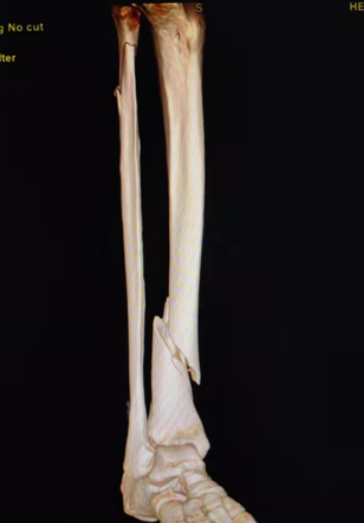

典型病例:女性,56歲,術前CT提示脛骨中下段骨折,移位明顯。

術后正側位片提示骨折達解剖復位,力線恢復正常。

術中照片可見手術切口約3厘米長,出血量約20ml。